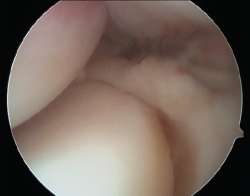

Baker et al.(29) describen 3 tipos de lesiones macroscópicas identificables mediante artroscopia exploradora de codo en los pacientes con epicondilitis (Figura 10):

- Tipo I: cápsula lisa sin irregularidades, inflamación y erosión en el tendón del músculo ECRB, sin muestras de desgarro completo.

- Tipo II: desgarros lineales o longitudinales en la cápsula por dentro de la superficie del origen del ECRB.

- Tipo III: lesión y retracción capsular con avulsión parcial o total del tendón del ECRB.

Aunque esta clasificación puede resultar útil a la hora de describir los cambios patológicos en la articulación, su valor pronóstico es limitado(30).